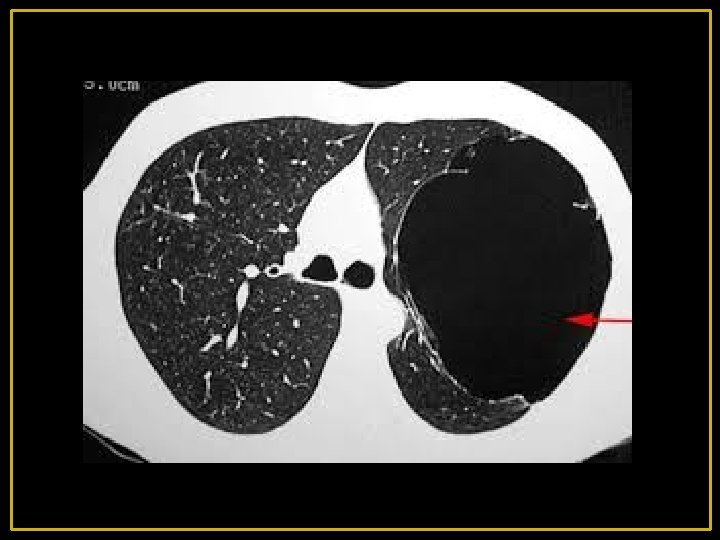

5 - Lésions bulleuses : Les lésions bulleuses peuvent se voir dans tous les types d’emphysème et particulièrement l’emphysème paraseptal. Elles sont dues soit à la confluence des lésions d’emphysème soit à la dilatation d’un territoire pulmonaire par un effet de clapet sur une bronche.